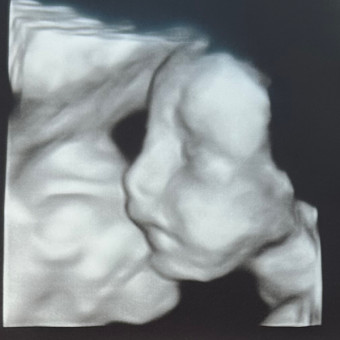

Baby Bradley’s registry

Paris Miller & Dylan Bradley

August 2, 2026